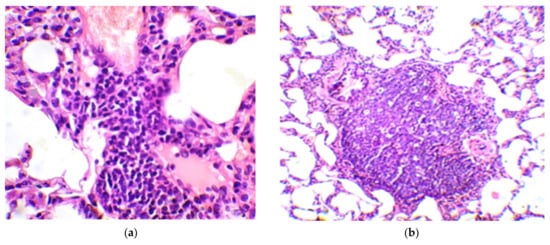

| Group No. | BCG Vaccine | Compound | Mean Follicle Area (µm2) | Mean Follicle Diameter (µm) | Follicle Size Distribution by Diameter (µm) | Number of Follicles of the Same Size (%) |

|---|---|---|---|---|---|---|

| 1 | − | − | 34,103.0 ± 2766.5 | 203.0 ± 8.8 | 70–100 | 3.3 |

| 110–160 | 23.3 | |||||

| 170–220 | 40.0 | |||||

| 230–270 | 26.7 | |||||

| 280–300 | 6.7 | |||||

| 2 | + | Betulinic acid | 37,478.8 ± 4532.1 | 216.3 ± 14.0 | 70–100 | 6.7 |

| 110–160 | 16.7 | |||||

| 170–220 | 33.3 | |||||

| 230–270 | 25.7 | |||||

| 280–300 | 16.7 | |||||

| 3 | + | Betulin | 19,080.7 ± 1905.0 1 | 147.0 ± 9.0 2 | 70–100 | 10.0 |

| 110–160 | 53.5 | |||||

| 170–220 | 36.7 | |||||

| 4 | + | Betulonic acid | 11,458.4 ± 1240.7 2 | 115.7 ± 6.5 2 | 70–100 | 43.3 |

| 110–160 | 46.7 | |||||

| 170–190 | 10.0 | |||||

| 5 | + | − | 20,742.3 ± 2386.4 1 | 155.0 ± 9.1 2 | 70–100 | 13.3 |

| 110–160 | 50.0 | |||||

| 170–220 | 23.4 | |||||

| 230–250 | 13.3 |